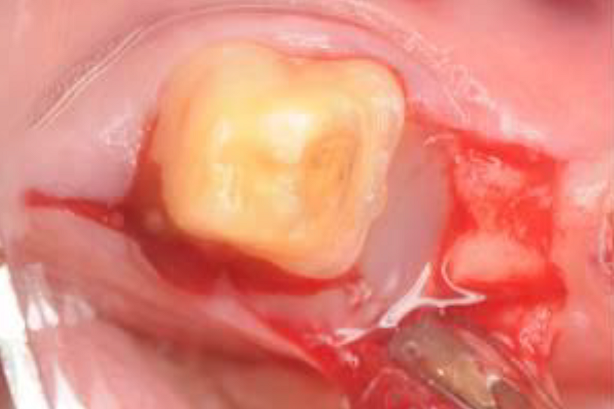

05/06 - Defect site and granules covered with Jason® membrane.Intrabony defect treated using Straumann® Emdogain®, cerabone® and Jason® membrane - Dr. D. B. Hangyási